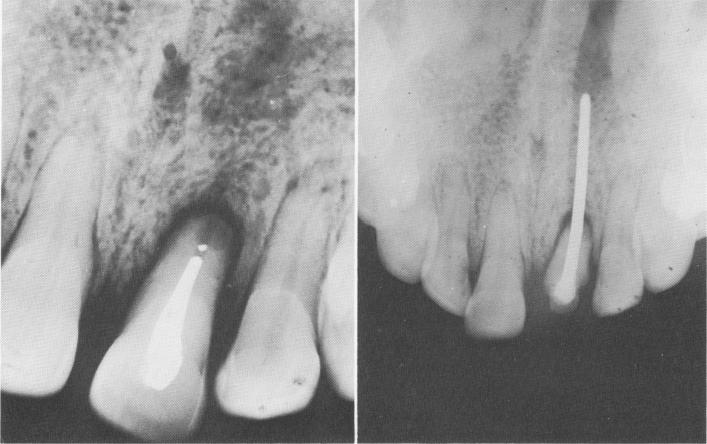

Fig. 13-22. Saving a reimplanted tooth. A few minutes after it was knocked out, this central incisor was root-treated (Wlakhoff method), reimplanted, and externally -splinted for about 4 weeks. A, Two years later the tooth was so loose that endodontic splinting was required. B, Five years after splinting, the tooth—which now carries an acrylic jacket crown—is a good member of the dental arch. (From Orlay, H. G.: Endodontic implants, J. Oral Implant Transplant Surg., pp. 44-53, 1965.)